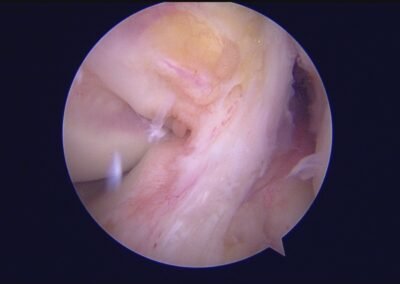

GalleryShoulder rotator cuff repair Meniscus root repair Meniscus repair Bankart repair for recurrent shoulder dislocation ACL reconstruction Machines Instruments